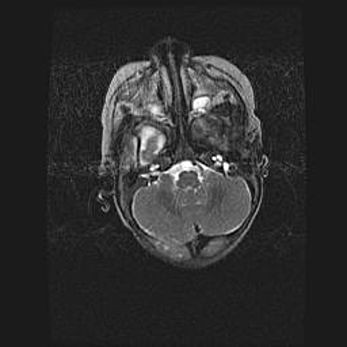

Мальформация Денди-Уокера. Киста задней черепной ямки.

Агенезия мозолистого тела.

Возраст: 2,5 месяца

Вес: 2420 г

Пол: женский

Окружность головы: 37 см

Срок гестации: 32 недели

Мальформация Денди—Уокера — редкий вид патологии ЦНС, представляющий собой врожденный порок развития каудального отдела ствола и червя мозжечка, ведущий к неполному раскрытию срединной (Мажанди) и латеральных (Лушка) апертур IV желудочка мозга. Для этогно синдрома характерна триада симптомов: гипотрофия червя мозжечка и/или полушарий мозжечка, кисты задней черепной ямки, гидроцефалия различной степени. В 70% случаев порок сочетается и с другими аномалиями головного мозга, в частности с агенезией мозолистого тела.